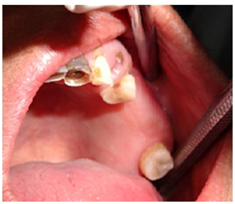

Incisional biopsy followed by surgical resection of the left posterior maxilla was done under general anaesthesia (Figure 6A‒6C). Histopathology revealed proliferating fibroblastic stroma without any mitotic activity and with the deposition of lamellar bone. Connective tissue stroma comprised of plump spindle shaped fibroblasts. Trabecular ossification showed osteoblastic rimming (Figure 7). The result of which confirmed the diagnosis of ossifying fibroma and the patient is under regular follow up.

Figure 7 Trabecular ossification showed osteoblastic rimming.